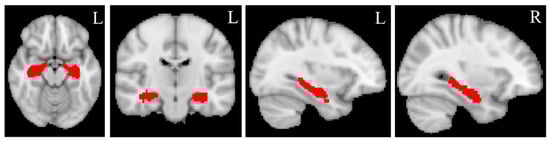

The binary masks of the bilateral hippocampus (Figure 2) were created from the automated anatomical labelling (AAL) atlas (https://www.gin.cnrs.fr/en/tools/aal/, accessed on 20 June 2022) [38], version 1, in the MNI space using “fslmath”, a function of FSL. MD and MK values for the bilateral hippocampus were extracted from the MD and MK maps in the standard space using the function “fslmeants” in FSL for each participant. Figure 3 displays the whole processing steps of DKI.

Figure 2.

Hippocampal masks. The bilateral hippocampal masks are created from Automated anatomical labeling (AAL) atlas, version 1, in standard MNI space using “fslmaths”, a function implemented in FSL. L = left, R = right. The red color represents the bilateral hippocampal masks.